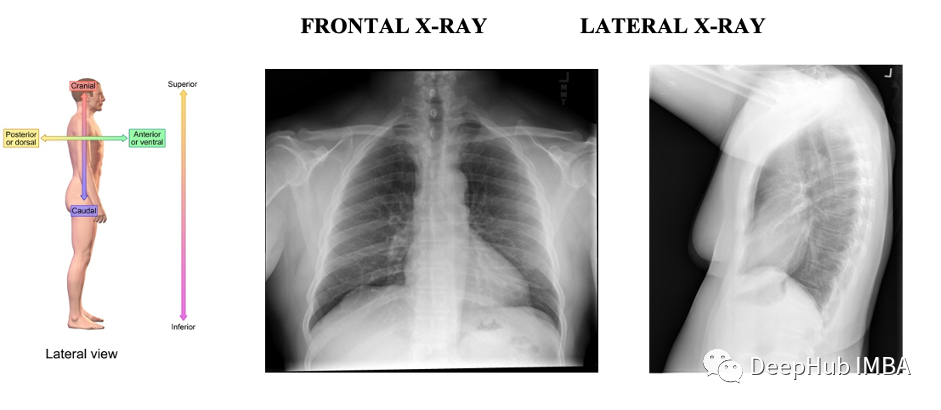

放射学中的图像描述

放射学也称为诊断成像,是一系列通过拍摄身体部位的照片或图像来诊断和治疗疾病的测试。虽然有几种不同的成像检查,但最常见的包括 X 射线、MRI、超声波、CT 扫描和 PET 扫描。

图像数据的信息如下:

数据大小:1.36 GB,图像数量:7470,所有图片均为png格式,可以直接使用OpenCV处理图像。所有的图像都有相同的宽度512像素。但是高度从362 p到873 px不等。

图像中包含了FRONTAL和LATERAL两个方向的x光